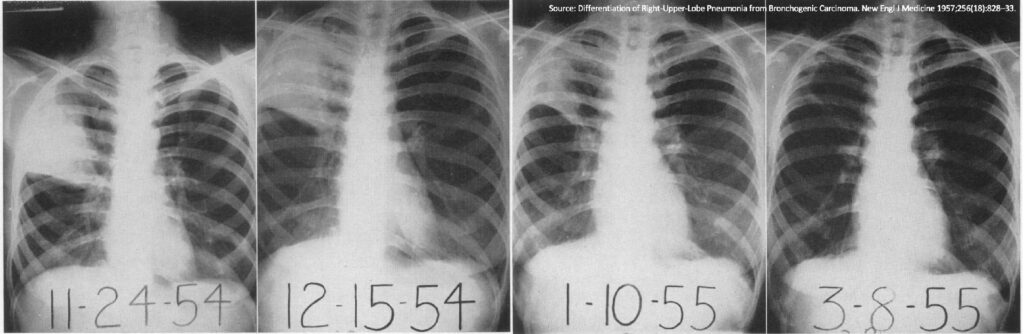

- Udelukkelse af Andre Sygdomme: Nogle gange kan en underliggende tilstand, såsom en blokeret luftvej eller i sjældne tilfælde en svulst, have forårsaget lungebetændelsen. Et opfølgende billede, der viser, at alt er normaliseret, hjælper med at udelukke sådanne alvorlige årsager.

- Helingsprocessen: Lungerne har brug for tid til at hele. Selvom du føler dig rask, kan der stadig være rester af betændelse, som vil tage flere uger at forsvinde helt fra et røntgenbillede.

- Symptomer forsvinder først: De fleste patienter oplever en betydelig lindring af symptomer, længe før de radiologiske tegn på infektionen er fuldstændig væk.

- Undgå fejlfortolkning: Hvis et billede tages for tidligt, kan de resterende skygger fra betændelsen fejlagtigt blive tolket som en vedvarende infektion, hvilket kan føre til unødvendig yderligere behandling eller bekymring.

Når det opfølgende røntgenbillede er taget, vil en radiolog nøje undersøge det for tegn på heling. De kigger efter, om de tidligere sete infiltrater (skygger) er blevet mindre eller er helt forsvundet. De ser også efter, om der er opstået nye fund, der kunne indikere en komplikation. Hvis der stadig er væske i lungehinden (pleuraeffusion), kan det kræve yderligere undersøgelse eller intervention. En klar og tydelig kommunikation mellem læge og patient om resultaterne er afgørende for den videre plan.